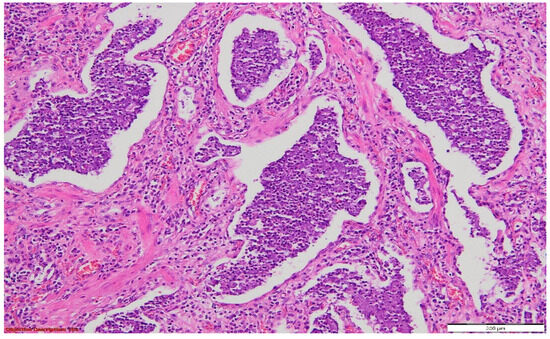

Figure 7. Pulmonary tissue with an enlarged bronchiolar lumen (bronchiectasis →), containing mucus and rare inflammatory elements; smooth muscle hyperplasia of the arterial media, and important polymorphous inflammatory infiltrate (predominantly lymphocytic) in the peri-bronchiolectatic interstitial parenchyma. HE, 40×.